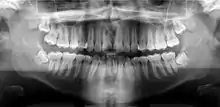

A panoramic radiograph of a 9 year old in mixed dentition